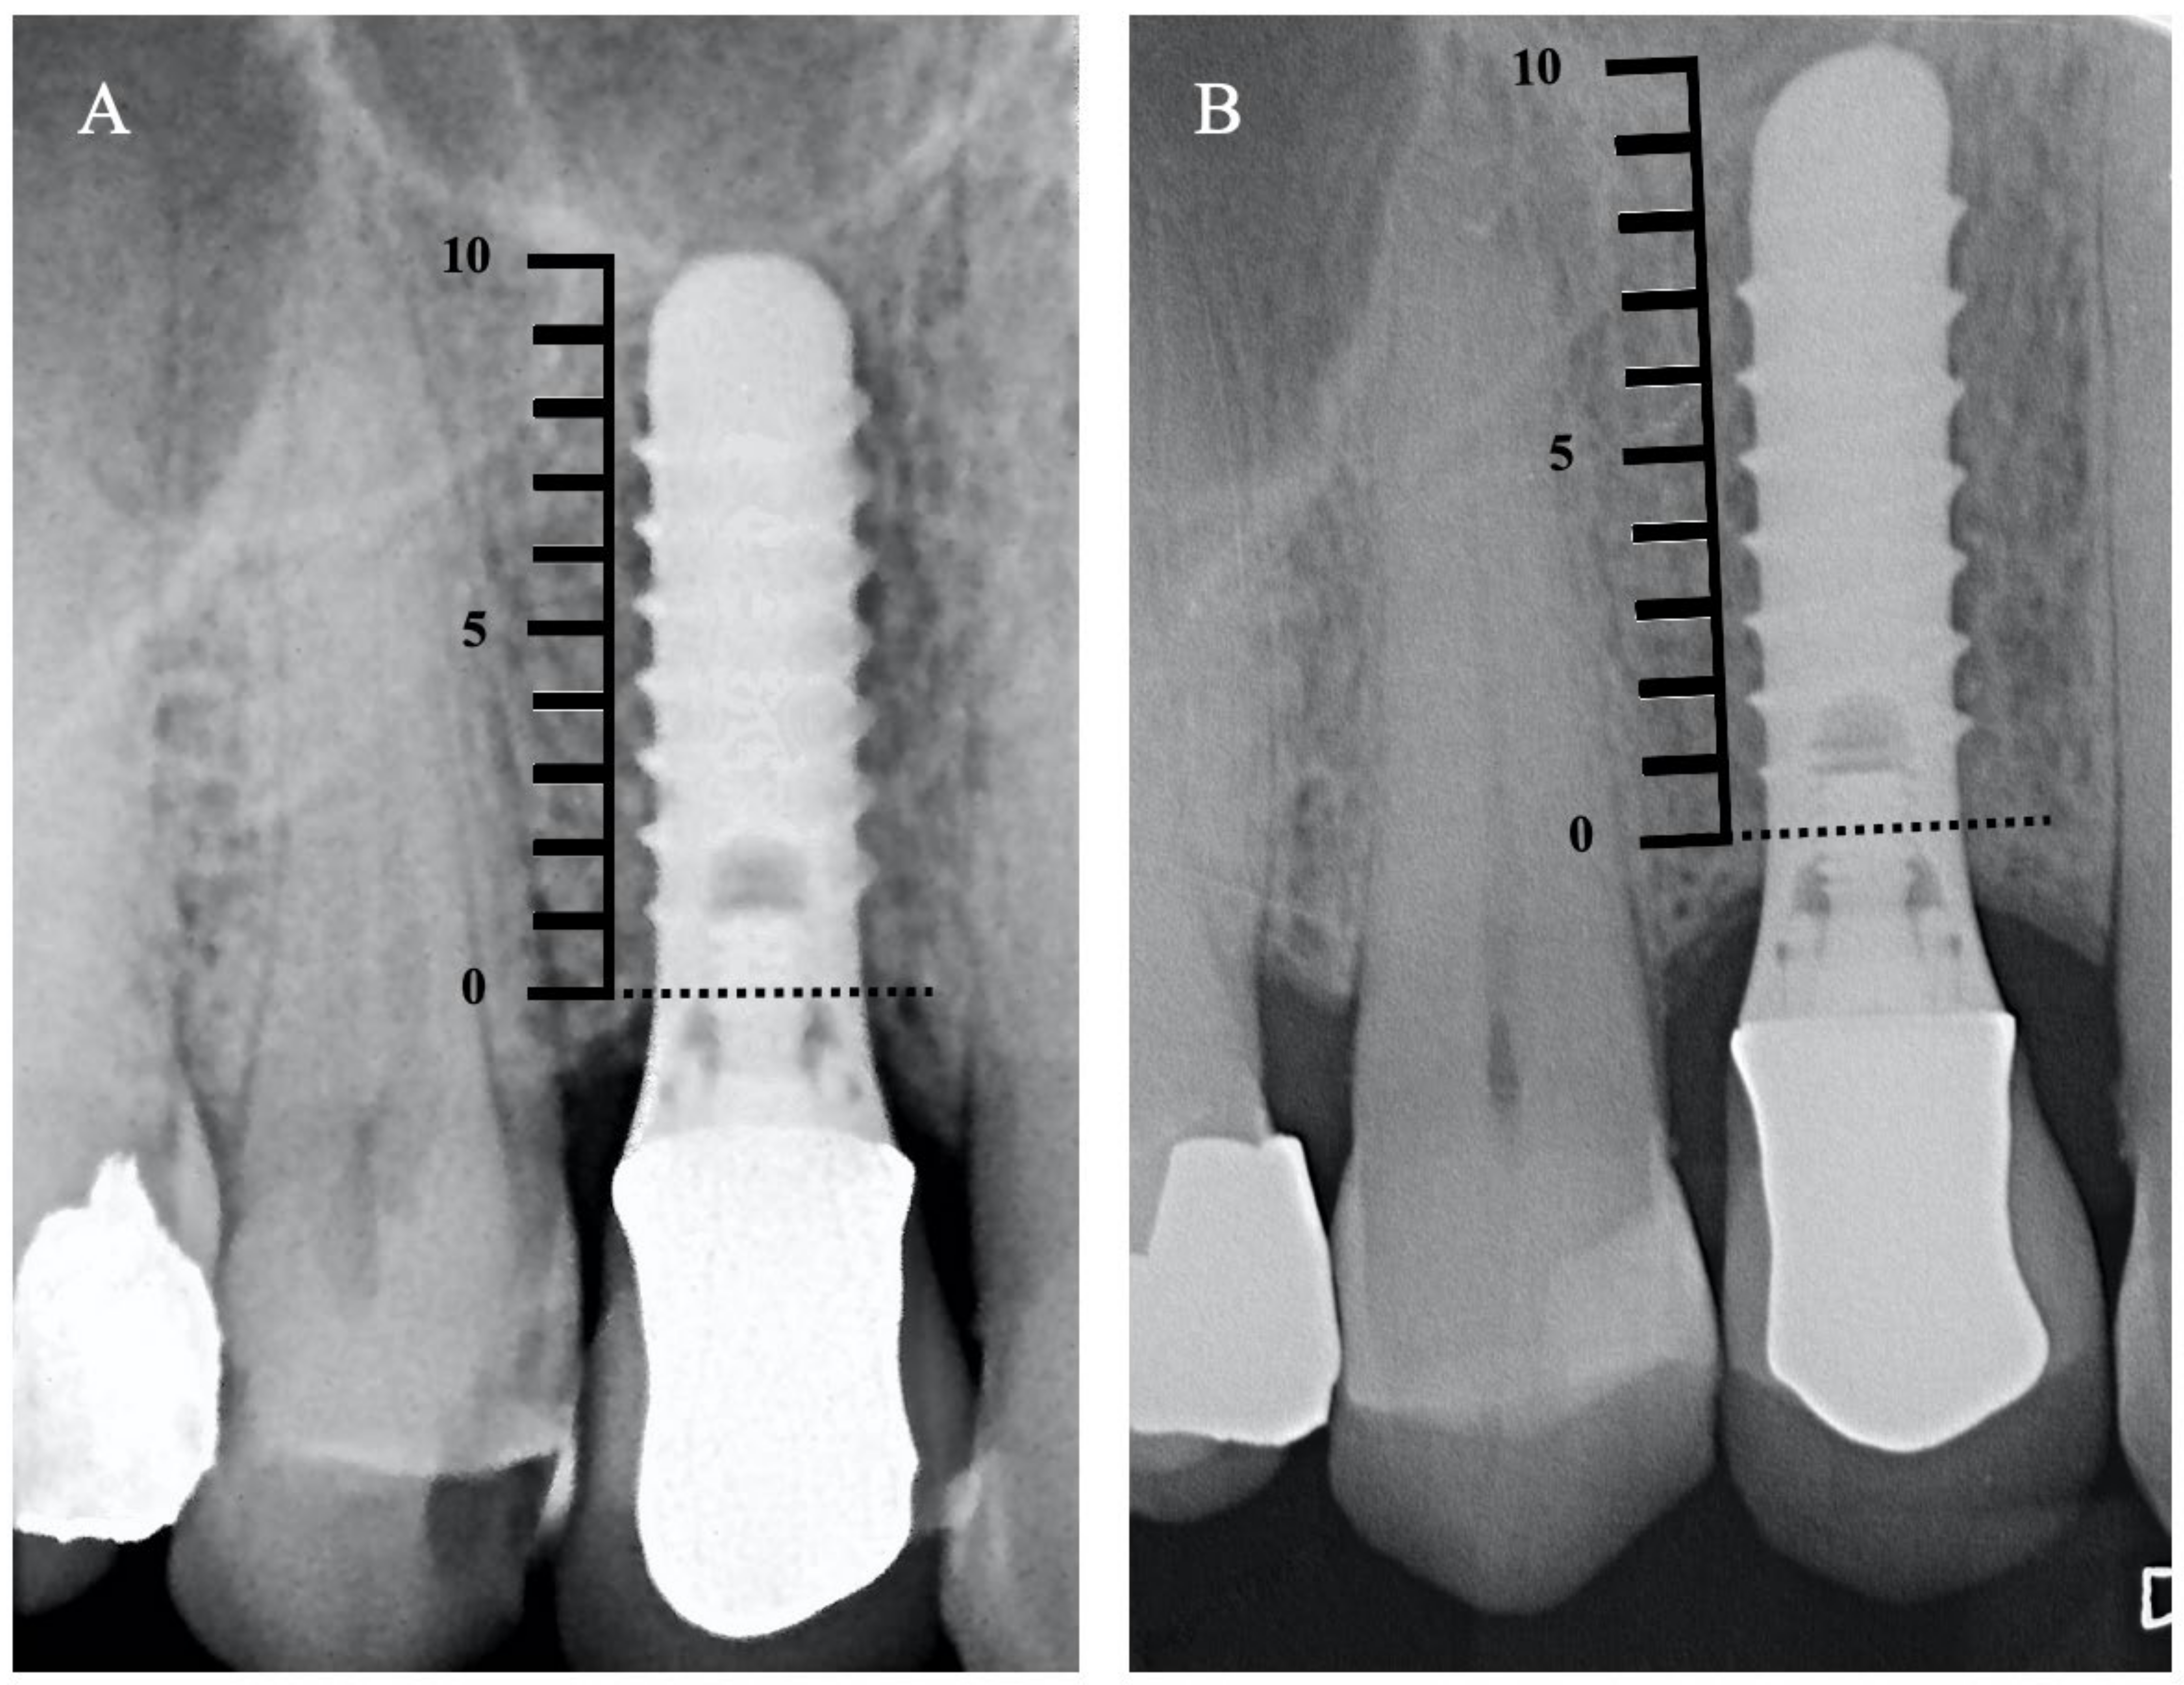

3.2. Clinical and Radiographic Analysis